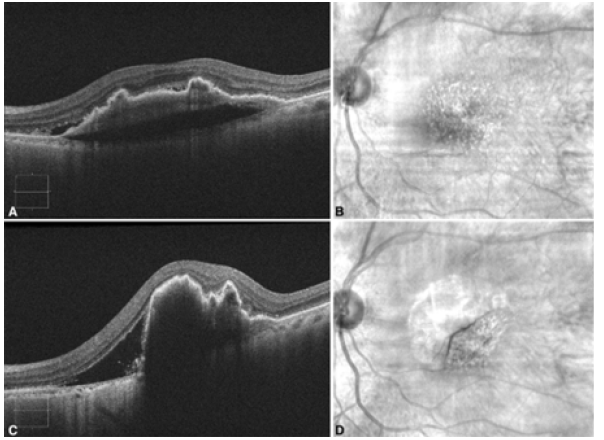

An 86-year-old female presented to the emergency department with a one-day history of worsened metamorphopsia in her left eye. This was in the setting of receiving a second intravitreal aflibercept injection (2mg/0.05ml injected 4.0mm posterior to the corneal limbus using a 30-gauge needle) in the left eye four days prior for nvAMD with a large, vascularized PED. The PED was 369μm at its highest point with subretinal fluid at the time of the injection (Figures 1A&1B) and the visual acuity on the left measured 20/40. However, in the emergency department, the patient’s visual acuity deteriorated to 20/60, and examination was significant for marked macular swelling with no evidence of other complications from the intravitreal injection, including retinal detachment. The patient proceeded to have optical coherence tomography (ZEISS Cirrus HDOCT, Carl Zeiss Meditec, Dublin, CA), which demonstrated increased PED height (837μm at the highest point) a new Grade 2 RPE tear (Figures 1C&1D).

Figure 1. A. Optical Coherence Tomography (OCT) image of the left eye demonstrating fibrovascular Pigment Epithelial Detachment (PED) with trace subretinal fluid on the same day as the intravitreal aflibercept injection; B. Corresponding red-free fundus photograph of the left eye; C. OCT image of the left eye demonstrating RPE tear with increased subretinal fluid and increased PED height post injection.; D. Corresponding red-free fundus photograph of the left eye demonstrating flap of RPE tear post injection.